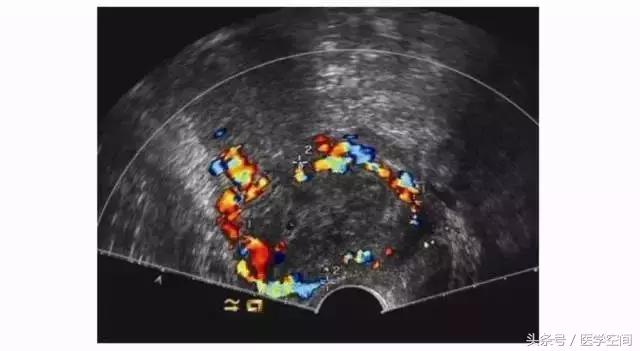

3.2CSP超声误诊的原因及临床后果

CSP超声漏诊进行了药流或人工流产、CSP自发流产不干净的患者,行超声检查时常表现为子宫剖宫产切口瘢痕处的不均质低回声肿块,CDFI在肿块周边常可探及丰富的血流信号(见图5),脉冲多普勒超声检查可探及低阻滋养动脉血流频谱,经验不足者可能会误诊为滋养细胞肿瘤,继而施以化疗。

图5不典型CSP的超声表现